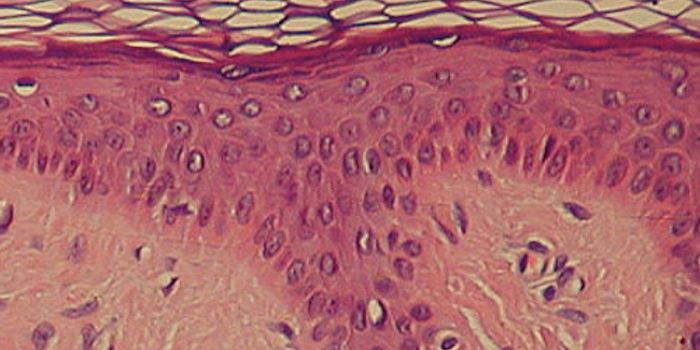

MAY 20, 2015CancerHeaded to the beach this summer? If yes, it is an essential for many of us to pack our favorite brand of sunscreen. Thin ...

MAY 26, 2023CancerBaz Luhrmann preached the importance of sunscreen to the ladies and gentlemen of the class of ’99 (and ever ...